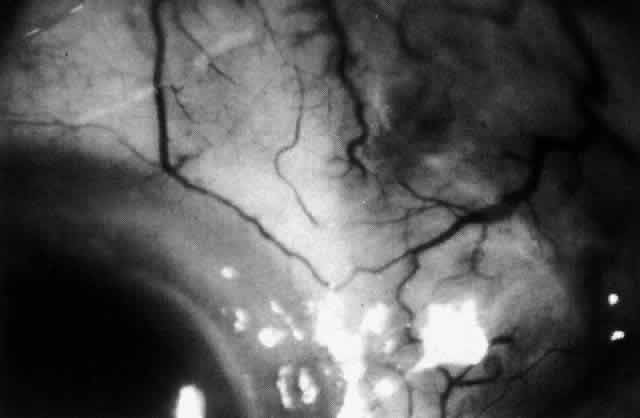

The characteristic features of necrotizing scleritis on fluorescein angiography are hypoperfusion and, eventually, nonperfusion of the vascular networks (Figs. 40 through 43).26 The initial changes are on the venous side of the capillary network; the transit time of the dye increases even if the eye is red and congested. If the disease process persists or has been present for a long time, thrombosis and permanent vaso-occlusive changes occur. These vessels (or the occluded capillary network) are bypassed by the opening of anastomotic channels. New vessels in a granuloma give rise to deep intrascleral leakage of dye (see Fig. 43). Conjunctival and episcleral involvement by the destructive change is late but is always preceded by vaso-occlusive changes that can sometimes be detected with use of the red-free light on the slit lamp (Figs. 44 and 45).

Fig. 42. Late arterial phase of fluorescein angiogram in a patient with necrotizing scleritis. All the vessels except the main trunk and the vessels around the limbal perforating vessels are occluded and remain unperfused throughout the angiogram.

Fig. 43. Late venous phase of angiogram of a patient with necrotizing scleritis showing late deep leakage from vessels on the surface of the sclera and leakage of the capillary network at the limbus and the vessels draining it, together with poor or absent perfusion of the remaining vessels.